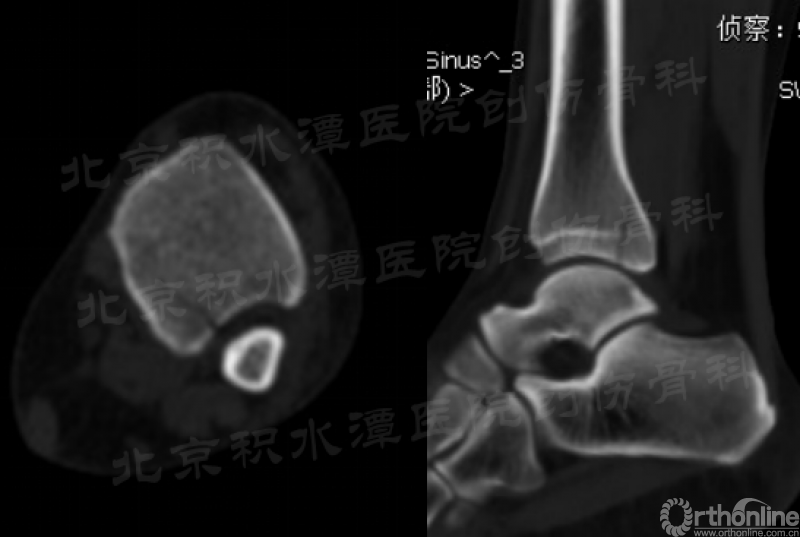

复查CT可见后踝骨折无移位(猜测当时踝关节处于跖屈位,制动电动车使左踝受到轴向应力),胫腓骨正侧位带膝未见腓骨近端骨折。